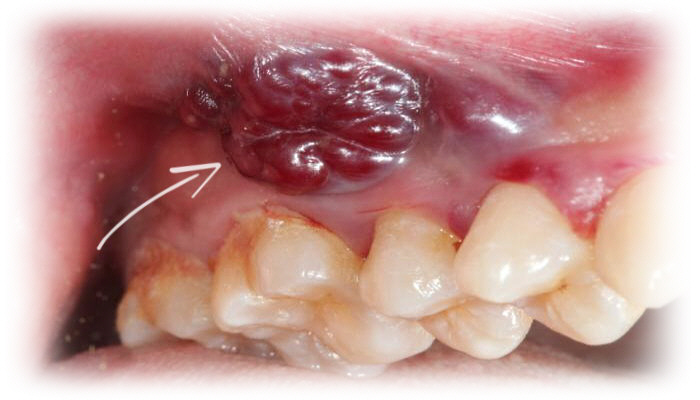

يعتقد الطبيب أنك مصاب بحالة مرضية تدعى:

سرطان الفم

ORAL MALIGNANCY